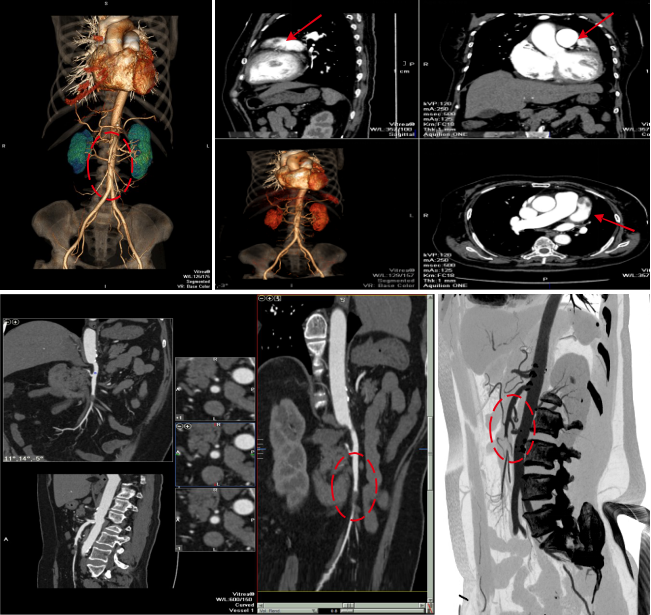

病例二 女,63歲,以持續(xù)性腹部疼痛不適半天就診。既往有冠心病15年、心房纖顫史5年余;高血壓5年。

采用心臟+主動(dòng)脈血管一站式檢查,可見(jiàn)該患者腸系膜上動(dòng)脈及其分支充盈缺損,同時(shí)顯示左心耳內(nèi)多發(fā)血栓, 隨時(shí)有血栓脫落的危險(xiǎn)。

全麻下行剖腹探查、 腸系膜上動(dòng)脈血栓取出術(shù), 病理顯示血栓樣組織機(jī)化。

患者術(shù)后第三天,由于右側(cè)肢體活動(dòng)障礙,語(yǔ)言受限,急查CT發(fā)現(xiàn)多發(fā)腔隙性腦梗塞,MRI檢查后明確左側(cè)急性梗死。

腸系膜上動(dòng)脈栓塞栓子多來(lái)源于心臟,也可來(lái)自于主動(dòng)脈壁粥樣硬化斑塊脫落。腸系膜上動(dòng)脈從腹主動(dòng)脈分出,主干口徑又較大,脫落的栓子易于進(jìn)入,在血管狹窄或分叉處導(dǎo)致血管栓塞。

臨床表現(xiàn)主要有“Bergan三聯(lián)征”1 、劇烈而沒(méi)有相應(yīng)體征的腹痛。2器質(zhì)性心臟病和并發(fā)心房纖顫的心臟病。3、胃腸排空障礙表現(xiàn)如腹瀉、 血便。

640層寬體探測(cè)器CT掃描速度快,可進(jìn)行大范圍心血管一站式檢查,快速排除血管病變,且由于探測(cè)機(jī)單元只有0.5mm,對(duì)于一些微小的病變也能清晰顯示。

病例三 男,54歲,10小時(shí)前無(wú)明顯誘因突然出現(xiàn)右側(cè)胸背部疼痛,呈脹痛,伴有大汗、頭暈癥狀。

腹盆腔CT腸道充氣成像可見(jiàn)橫結(jié)腸脾曲結(jié)腸癌, 升結(jié)腸及降結(jié)腸多發(fā)息肉

腹腔鏡見(jiàn)腹腔粘連較重, 轉(zhuǎn)開(kāi)腹手術(shù), 取左側(cè)腹直肌切口, 逐層進(jìn)腹, 于橫結(jié)腸脾曲觸 及一腫塊, 遂行左半結(jié)腸切除術(shù)。

640層寬體探測(cè)器CT掃描速度快, 掃描時(shí)間只用了2 . 3 s,克服了胃腸道蠕動(dòng)造成的偽影 和漏層, 使腹部圖像質(zhì)量大大提高。 仿真內(nèi)窺鏡的圖像可觀察到黏膜的皺襞 , 不僅可清晰的 顯示小息肉及病變 , 而且可顯示出胃腸道造影及內(nèi)窺鏡易于遺漏的部位。